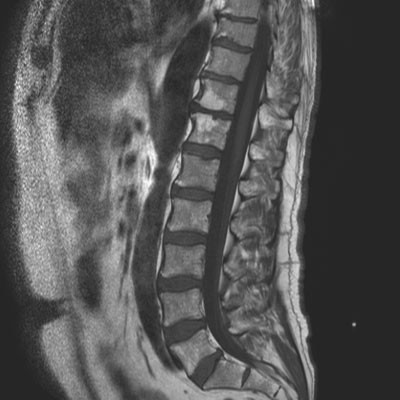

MR medulla uten kontrast dagen etter viste bare lette degenerative forandringer i torakalcolumna (fig 1).